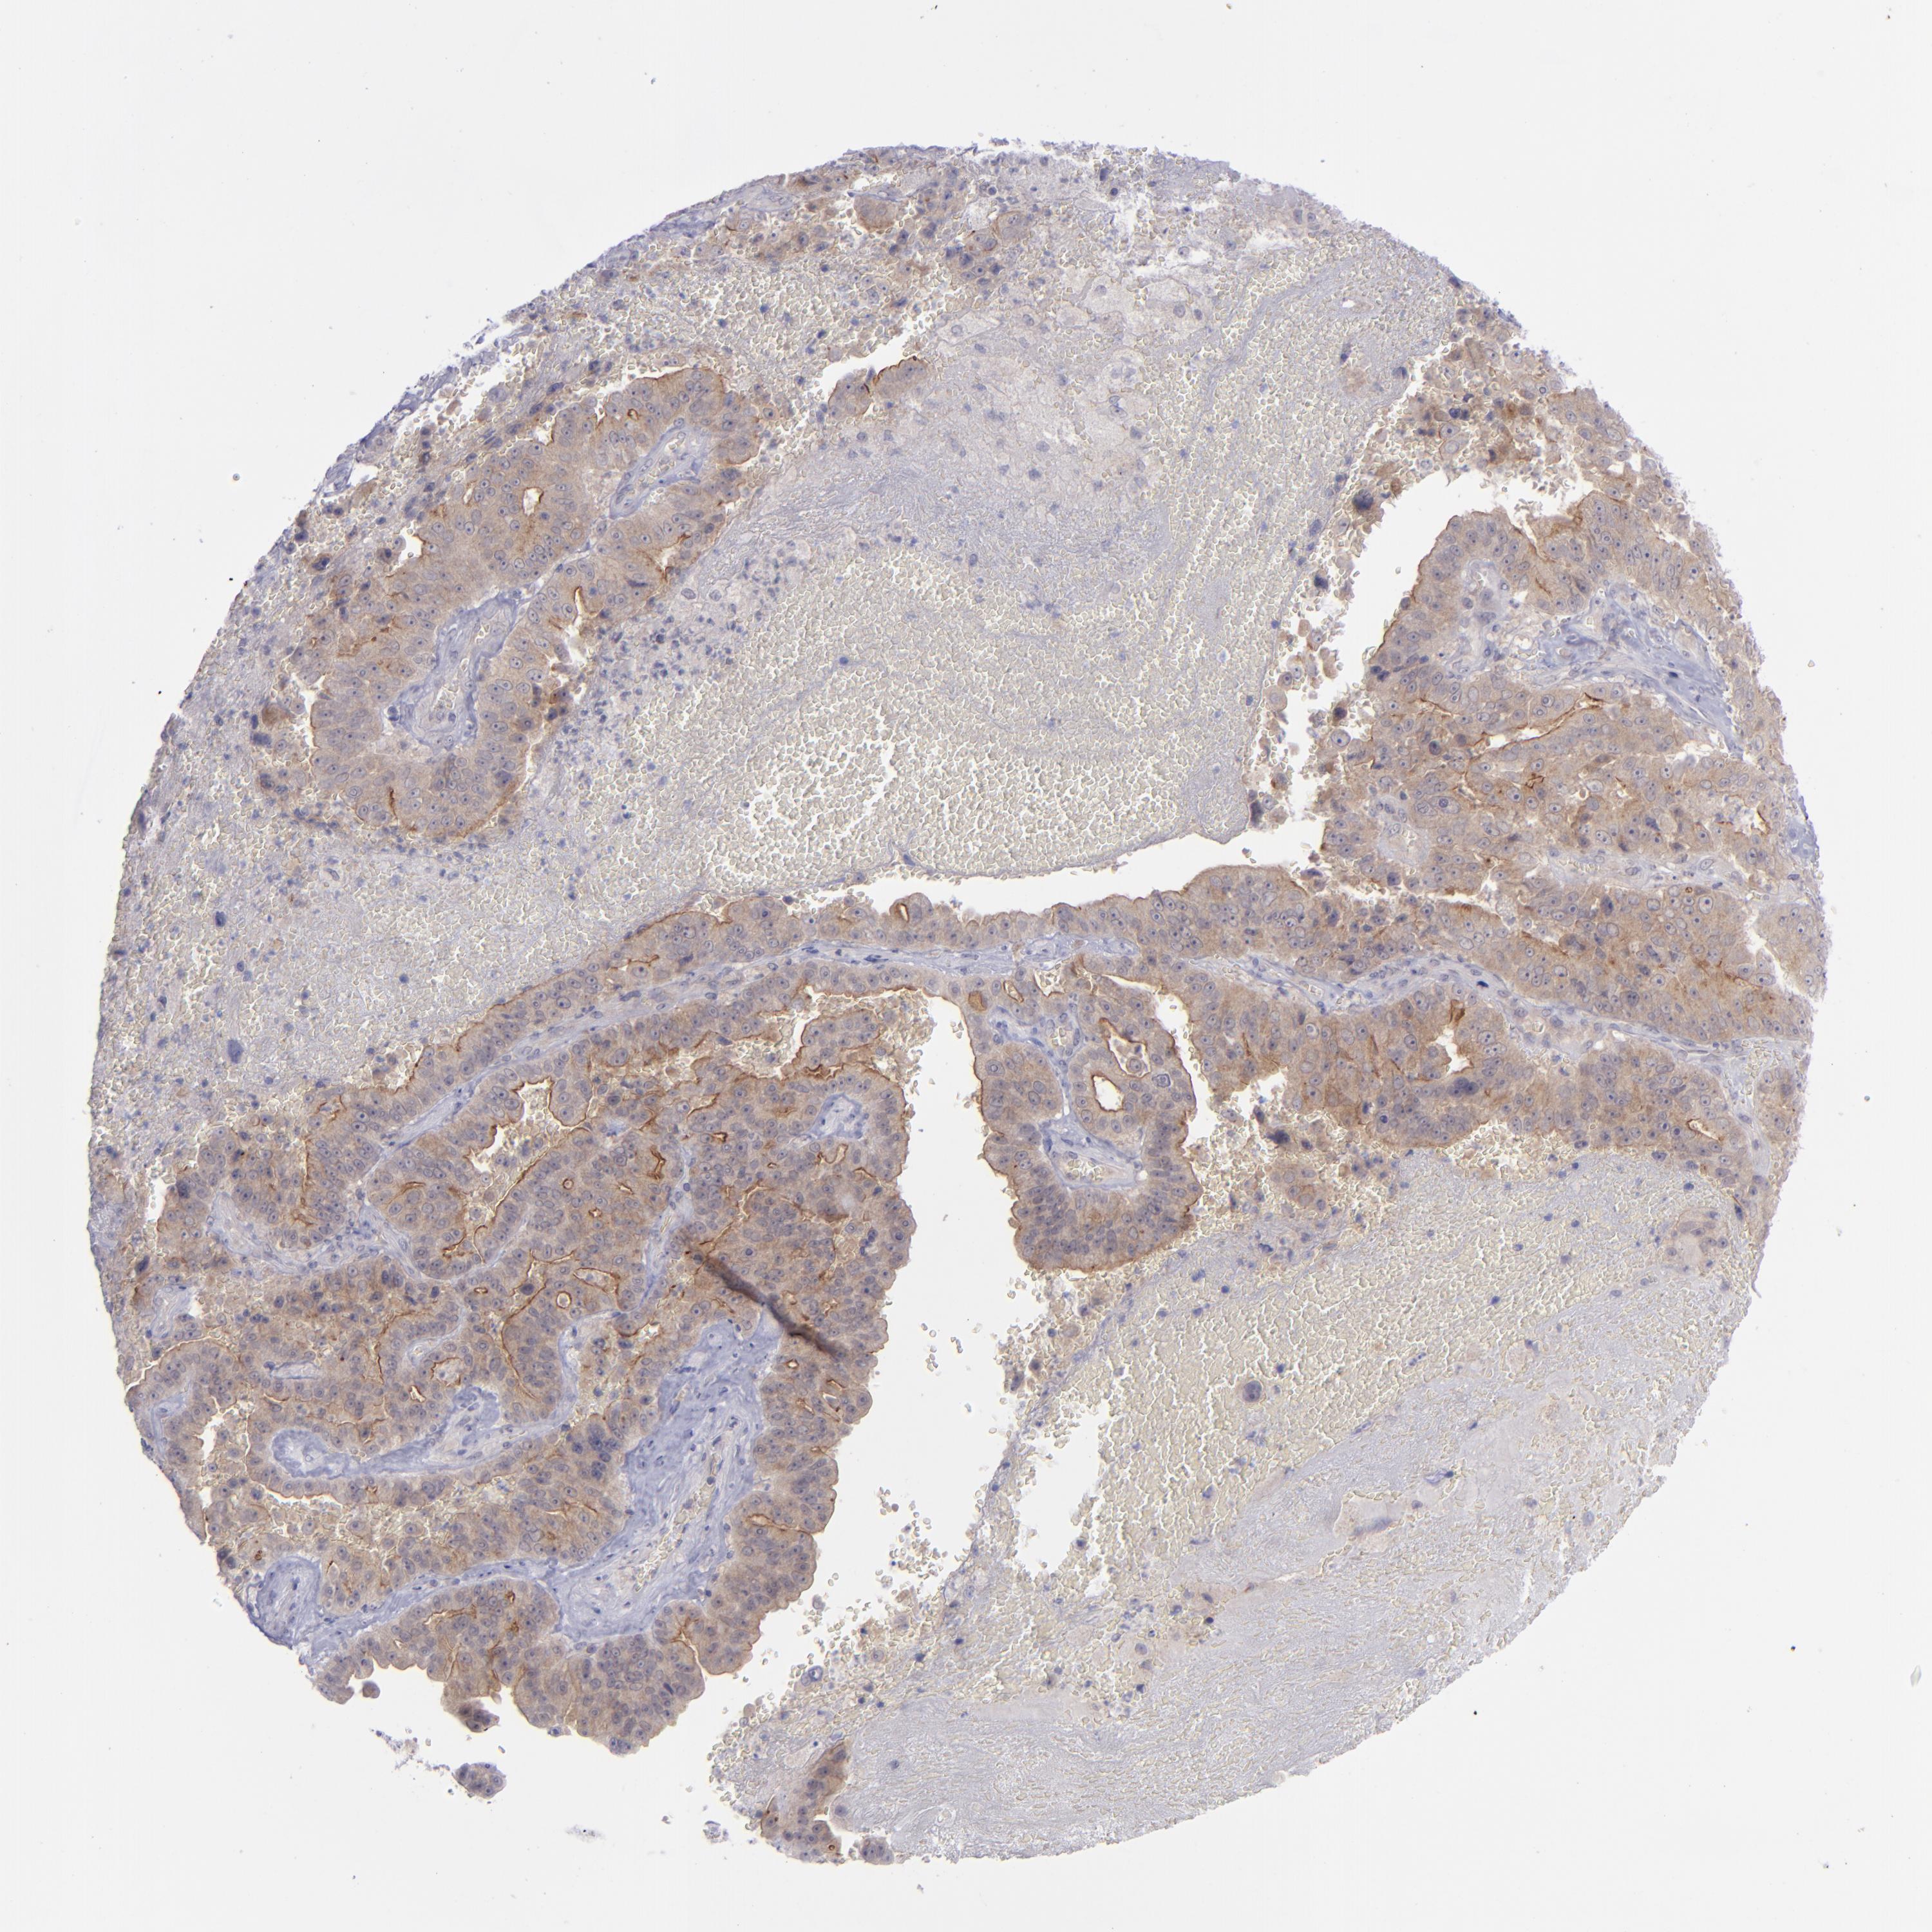

LIVER CANCER - Protein expressioni

A mouse-over function shows sample information and annotation data. Click on an image to view it in a full screen mode. Samples can be filtered based on level of antibody staining by selecting one or several of the following categories: high, medium, low and not detected. The assay and annotation is described here.

Note that samples used for immunohistochemistry by the Human Protein Atlas do not correspond to samples in the TCGA dataset.

Antibody stainingi

Antibody staining in the annotated cell types in the current human tissue is reported as not detected, low, medium, or high, based on conventional immunohistochemistry profiling in selected tissues. This score is based on the combination of the staining intensity and fraction of stained cells.

Each image is clickable and will lead to virtual microscopy that enables deeper exploration of all samples and also displays staining intensity scores, fraction scores and subcellular localization as well as patient and tissue information for each sample.

Antibody CAB002220

Staining

High

Medium

Low

Not detected

Intensity

Strong

Moderate

Weak

Negative

Quantity

>75%

75%-25%

<25%

None

Location

Nuclear

Cytoplasmic/membranous

Cytoplasmic/membranous,nuclear

Carcinoma, Hepatocellular, NOS

Cholangiocarcinoma